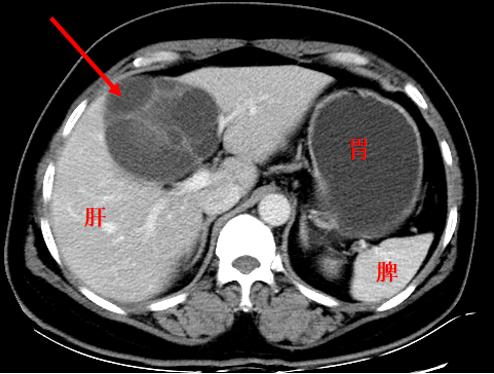

与前图相似,但却是真肿瘤(囊腺瘤)

大多数的肿瘤表现为肿块,可为实性肿块(如纤维瘤、脂肪瘤、畸胎瘤,肺癌、肝癌、肠癌等),可为囊性肿块(如卵巢囊腺瘤、囊性肾癌等),也有的表现为囊实性肿块(如神经鞘瘤、囊腺癌等)。但也有些肿瘤如白血病、淋巴瘤等,很可能就找不到肿块,而是需要通过血液检查甚至是骨髓穿刺才能诊断。